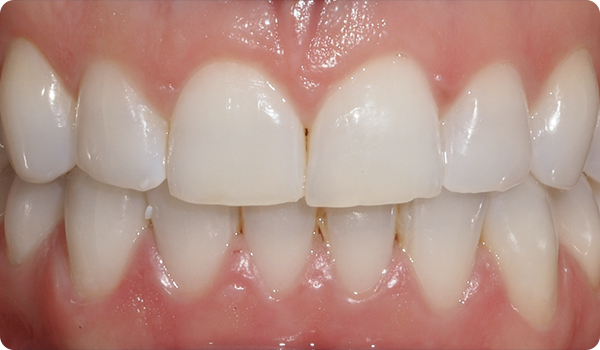

Med Right får dine patienter det smil, de ønsker, inden for den ønskede tid, på en komfortabel og "usynlig" måde.

At justere tænder med Right er den perfekte og mest skånsomme forberedelse til fremtidig tandblegning eller facadebehandlinger, der vil perfektionere patientens smil.